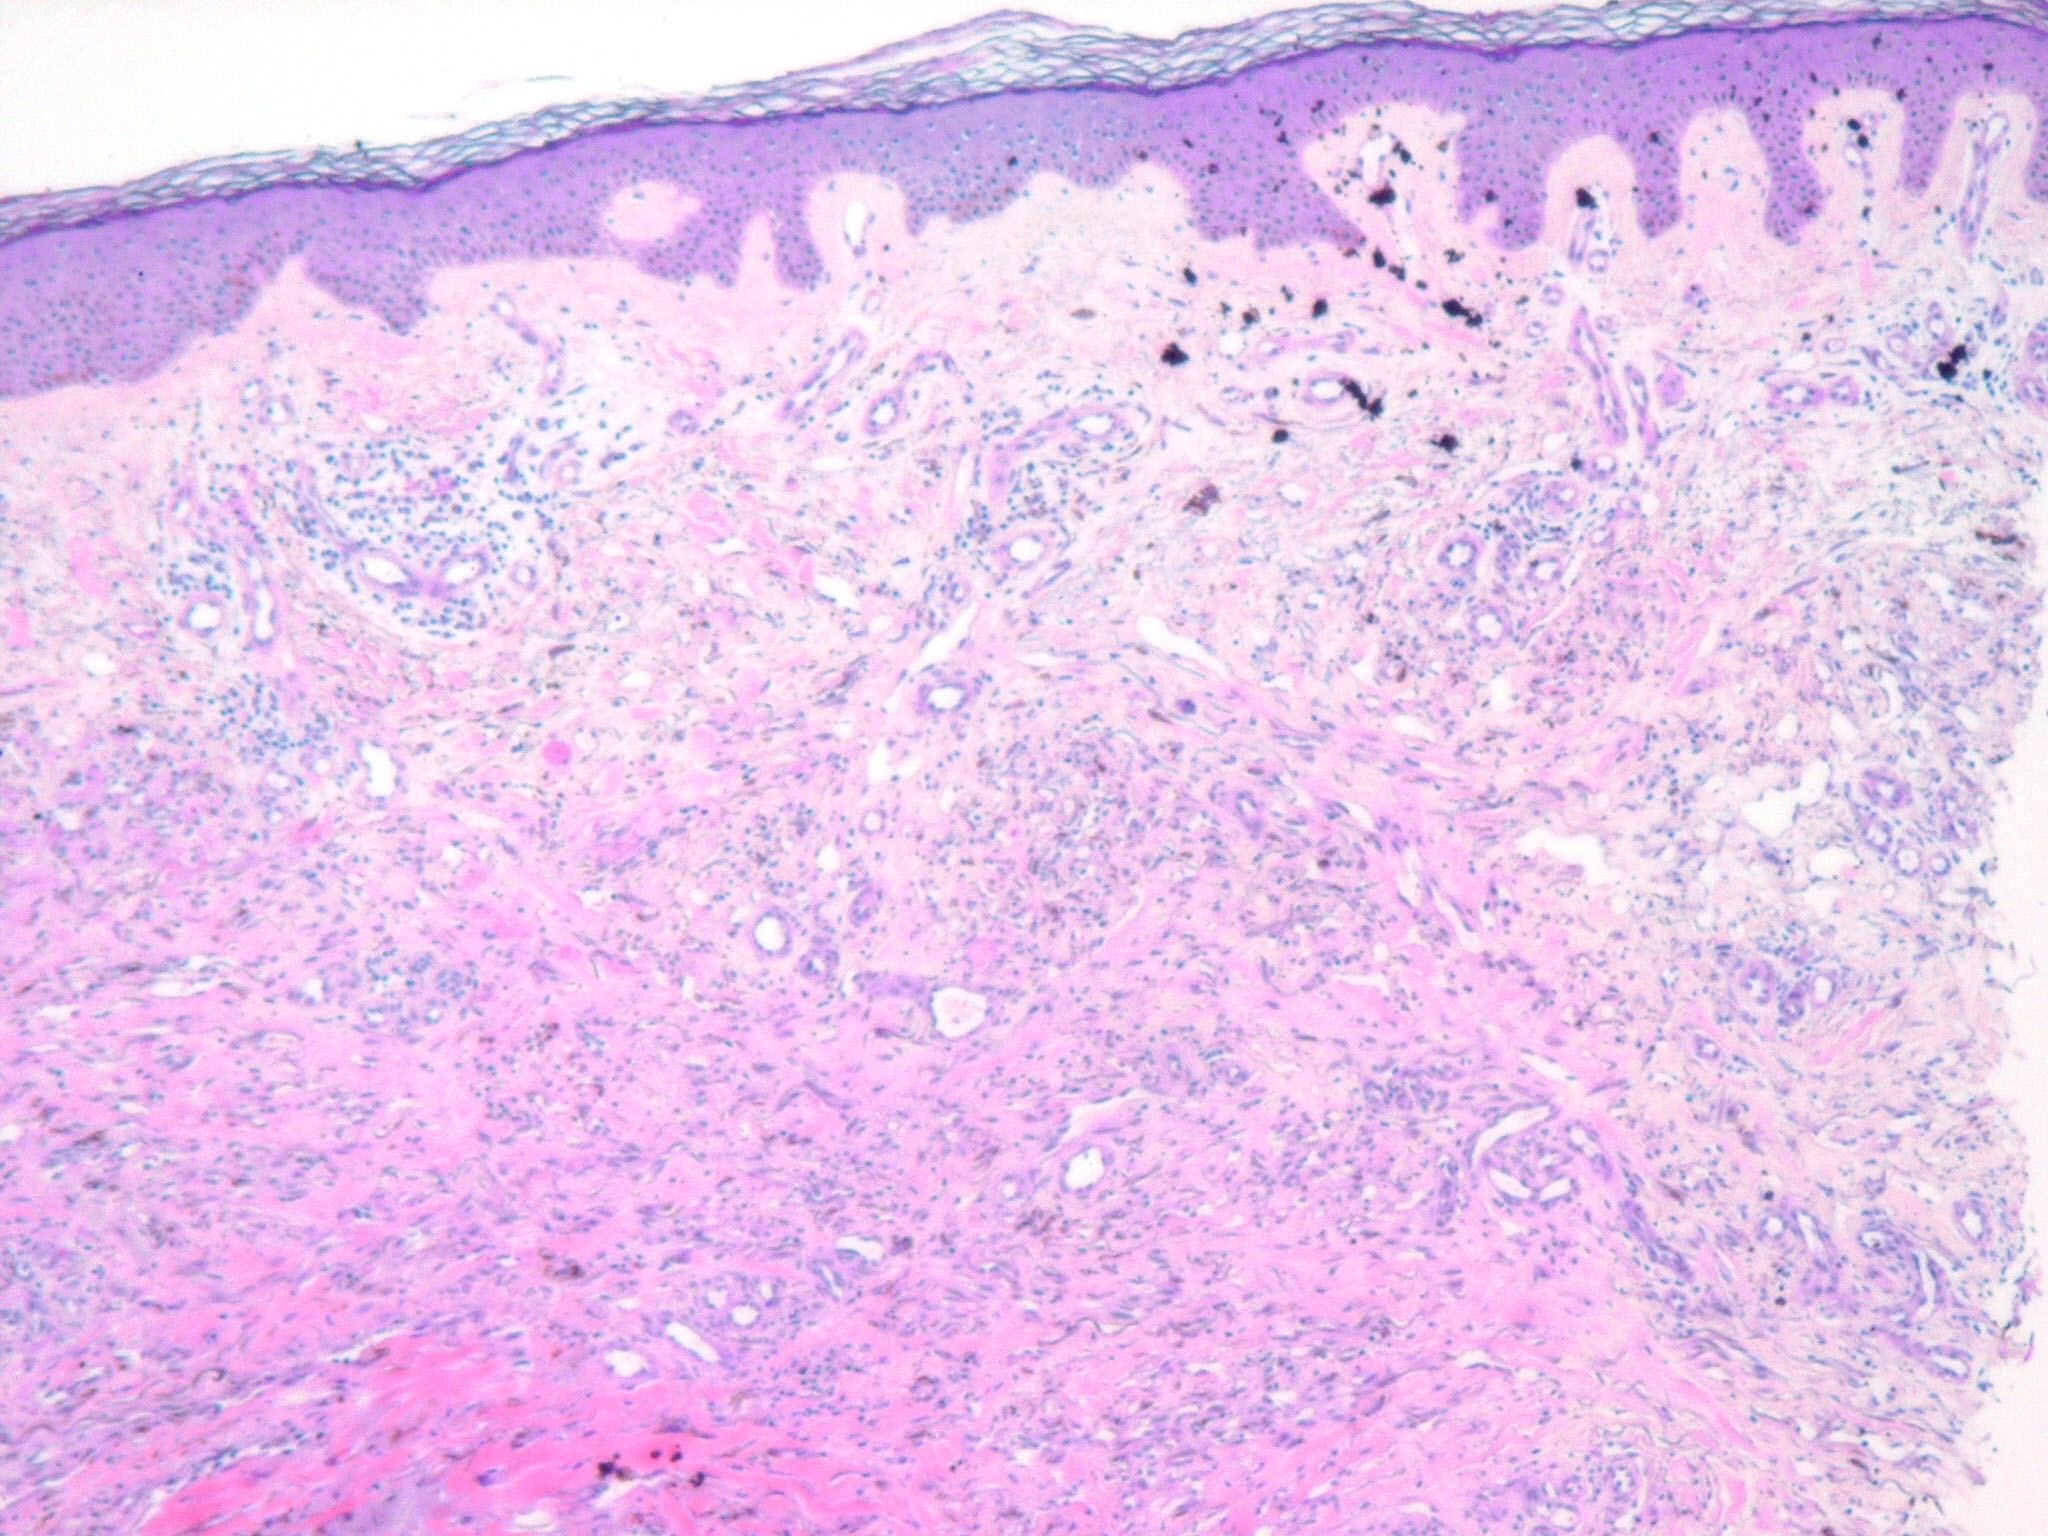

HISTOPATHOLOGY

The histopathology of KS is dependent on the stage of KS development. Early patch-like lesions exhibit rather discrete histopathologic changes, consisting mainly of an increase in the number of dermal vessels, outlined by slightly irregular endothelial cells (Fig. 128-5). These vessels, located mainly in the superficial dermis are parallel to the skin surface, are frequently slightly irregular, and may form bizarre slits and clefts. In the surrounding skin focal hemosiderin, deposits and extravasated erythrocytes can be found as well as a moderate inflammatory infiltrate. Important differential diagnoses of this stage include lymphangioma and granulation tissue.

The pathology of KS plaques is more characteristic and reveals extensive vascular proliferation at all levels of the dermis with multiple dilated and angulated vascular spaces dissecting the collagen leaving a spongy network of collagen tissue. A characteristic sign of KS papules is the presence of solid cords and fascicles of spindle cells arranged between the jagged vascular channels. This biphasic angiomatous and solid tumor morphology changes to a clear-cut sarcomatous morphology with progression of the disease.

Nodular lesions consist predominantly of spindle cells arranged in bundles and interlacing fascicles and interspersed, irregular, slit-like vascular spaces without endothelial linings. Advanced lesions may display pronounced pleomorphism, nuclear atypia, and mitotic figures. At the periphery of solid tumors, (lymph) angiomatous-like portions of KS with bizarre vascular lumina and intravascular and extravasated erythrocytes, as well as siderophages, may be preserved. Erythrocytes, which appear as eosinophilic globules, are trapped within the slits and clefts formed by the spindle cells and erythrophagocytosis are occasionally observed. As in all other stages of KS, a moderate inflammatory infiltrate consisting of lymphocytes, histiocytes, plasma cells, and, sporadically, neutrophils is regularly present.